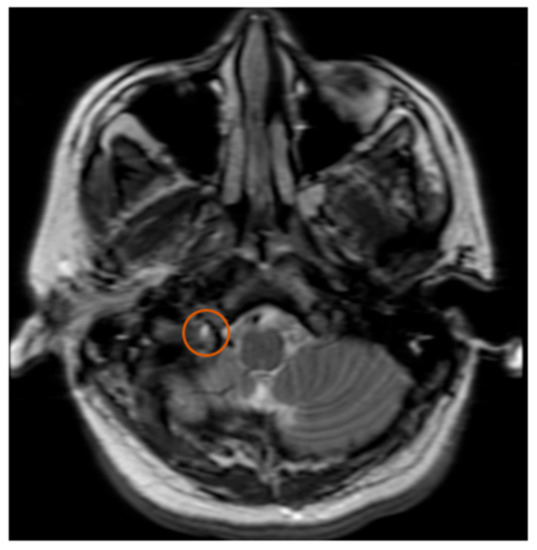

Collet–Sicard Syndrome has rarely been described as a consequence of blunt head trauma. Injuries to the jugular foramen and the hypoglossal canal are rare, as most blunt head traumas resulting in basilar skull fracture involve the condyles. In most cases, the condition is self-limiting, with patients regaining most to all of their neurological functions within 6 months. Several theories have been proposed for the pathophysiology of this syndrome. Displaced bony fragments that could compress the nerves in the context of fracture extension to the posterior jugular foramen or to the hypoglossal canal has been one theory to explain the neurological manifestations seen with CSS [6]. Bridgman et al. suggested that the cranial nerves were damaged by traction injuries [7]. Orbay et al. reported a case in which hypoglossal nerve palsy occurred 3 months after a head injury and suggested that a scarring process and the formation of a callus at the level of the hypoglossal canal could progressively compress the main hypoglossal nerve [8]. One of the more recent theories is that soft tissue edema, as a consequence of the local injury, compresses the cranial nerves (9, 10, 11 and 12) and leads to their deficits. With time, as the edema resolves, the neurological deficits also resolve [9]. The initial fracture, as can be seen by Figure 1, demonstrates a fracture on the border between the jugular foramen and the hypoglossal canal. CT of the Temporal bone better demonstrates the fracture location (See Figure 2). A subsequent MRI of the brain also demonstrates an area of hypo-attenuation, consistent with edema at the location of the jugular foramen and the hypoglossal canal (Figure 3). Treatment for CSS with blunt head trauma remains conservative, as other causes, such as a tumor or vascular impingement, require treatment of the underlying cause. As the edema resolves, so do neurological deficits. Some authors have advocated the anecdotal use of steroids to reduce the edema; however, as this case is very rare, large multi-institutional trials are warranted to better elucidate the role of steroids with Collet–Sicard syndrome. Of important note is to readily identify this condition and provide nutritional support with feeding tubes, as the recovery time is generally 3–6 months. In conclusion, injuries with focal neurological deficits which were not apparent on initial imaging should be reviewed by relevant experts with concomitant knowledge of the patient’s history and experience in neuroimaging.

Figure 3. MRI T2. Orange circle indicates edema at the junction of the Jugular Foramen and the Hypoglossal Canal.